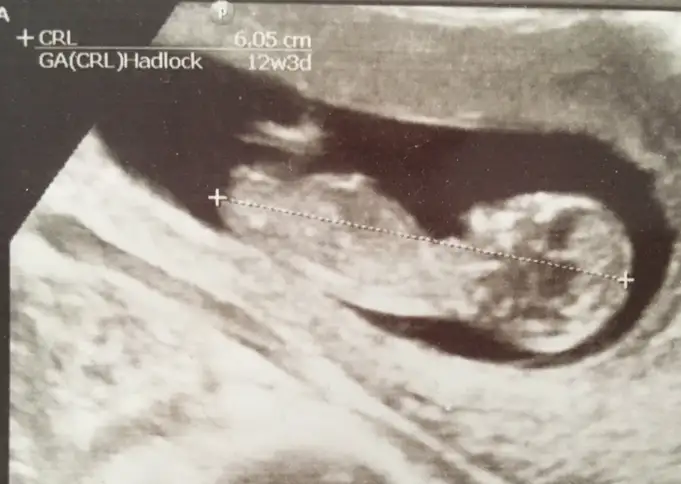

12+0 ama boyundan dolayı 12+3 çıkmıştı o gün :)Erkek gibi :)

Kaç haftalık burda canım bizim niye böyle net çıkmıyo ya ultrason resmimiz :)

Maşallah diyelim12+0 ama boyundan dolayı 12+3 çıkmıştı o gün :)